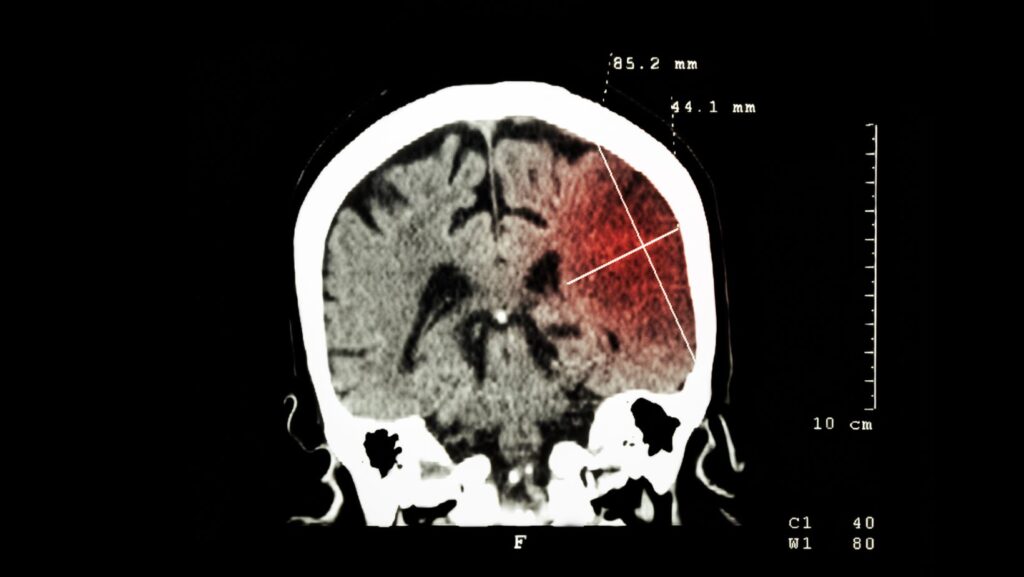

뇌혈관이 막혀 발생하는 허혈성 뇌졸중 증상이 나타난 후 48시간 이내에 신경 보호 신약 물질을 투여하면 뇌세포 보호와 회복 효과를 얻을 수 있다는 무작위 대조 임상시험 결과가 나왔다.

9일 미국 심장 협회(AHA)에 따르면 신경보호 신약물질 ‘로베라미살'(loberamisal)과 위약을 뇌졸중 증상 발생 후 48시간 이내에 시작해 10일간 매일 정맥 주사로 투여하는 무작위·이중맹검·위약 대조 제3상 임상시험에서 로베라미살 투여 그룹이 위약 그룹보다 90일 시점에서 우수한 기능적 회복을 보였다.